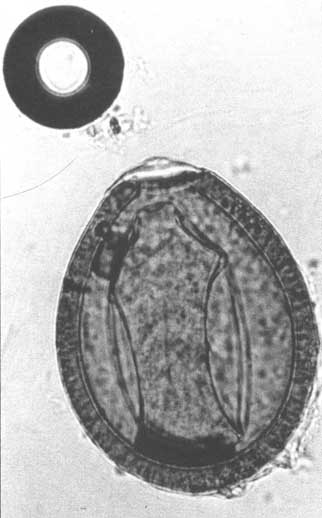

Oocyst of an Eimeria sp. infecting camels - Oocyste d'Eimeria sp. infectant les chameaux - Oocisto de Eimeria spp. presente en camellos